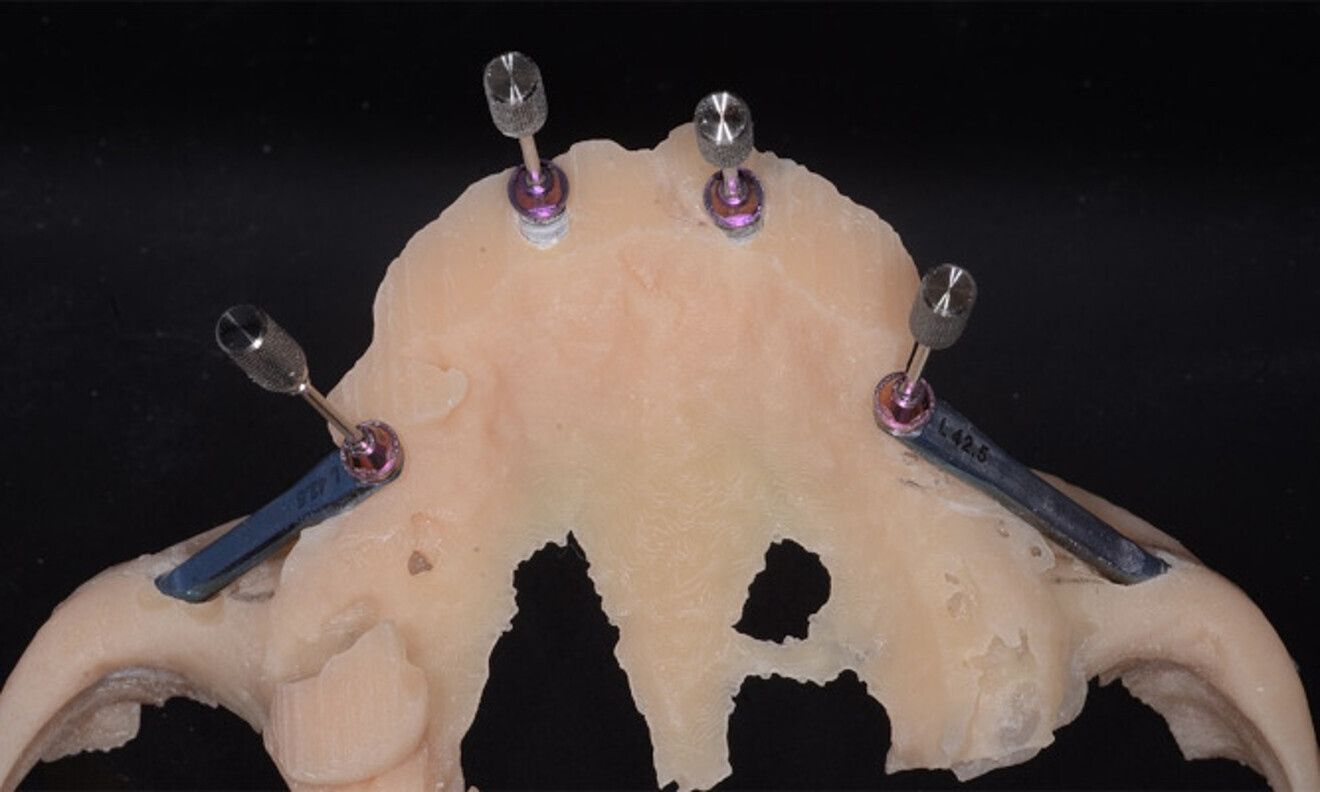

The treatment was carried out under local anaesthesia with 2% lidocaine and 1:100,000 adrenaline. A crestal incision was made and a full-thickness mucoperiosteal flap raised. The implant beds were prepared with the Straumann Surgical Cassette, and two Straumann BLX implants (4.5 × 10.0 mm, SLActive, Roxolid) and two Straumann zygomatic implants (4.3 × 40.0 mm) were placed in the maxilla (Fig. 8). Following the same protocol, four Straumann BLX implants (4.5 × 10.0 mm, SLActive, Roxolid) were inserted in the mandible. Straumann screw-retained abutments were positioned on to the implants (Fig. 9).